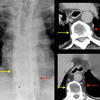

AzyEsop interf

Ex 1 arrows